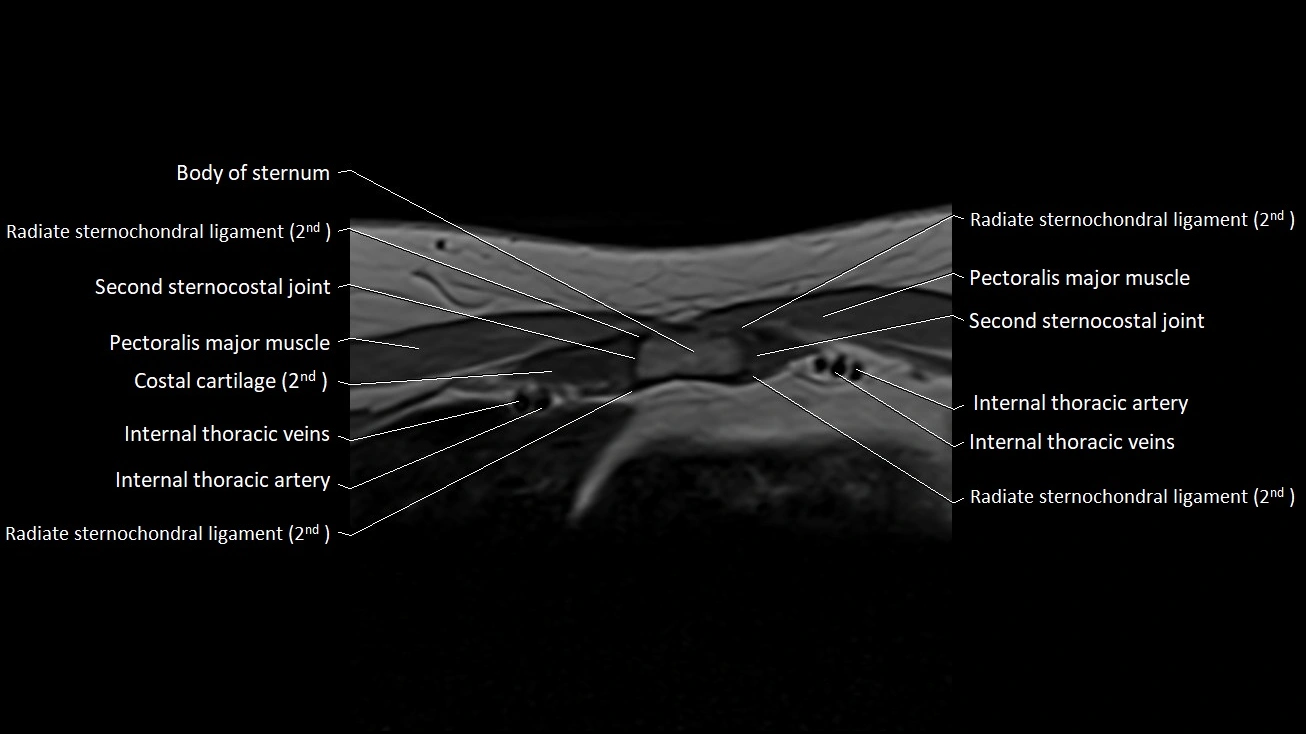

MRI images

image